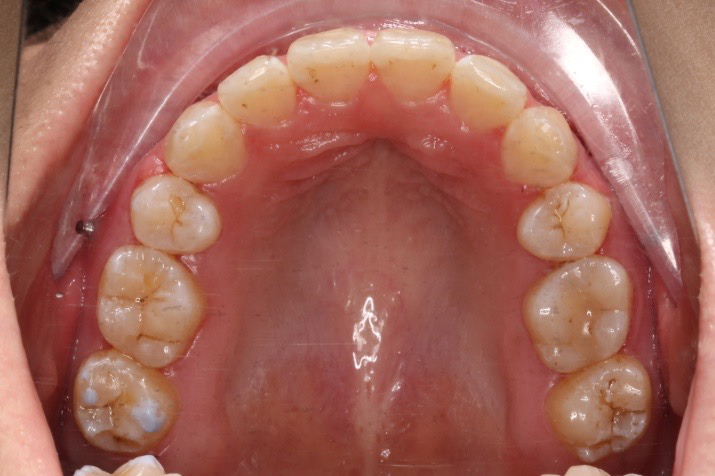

IntraoralExamination(2016-08.31,Wu)

• 磨牙,尖牙I类关系,中线齐

• 上下牙列中度拥挤

• 上下前牙唇倾